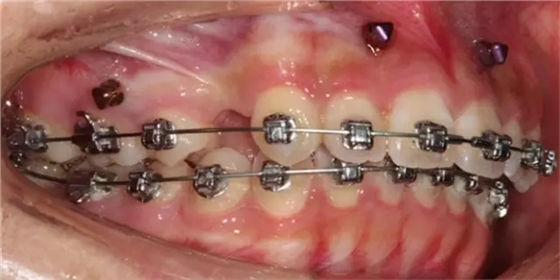

上下牙列擁擠,磨牙尖牙Ⅱ 類關(guān)系,3 度的深覆牙合,上頜中切牙伸長內(nèi)傾拔除上頜雙側(cè)的第一前磨牙,先粘上頜高轉(zhuǎn)矩的自鎖托槽排齊牙列,唇向開展上頜切牙,有一定的覆蓋,粘下頜標準轉(zhuǎn)矩托槽,上頜 1, 2 之間植入種植支抗壓入,同時后牙 5, 6 之間植入種植支抗內(nèi)收前牙,打開咬合關(guān)閉間隙。治療關(guān)鍵:前牙轉(zhuǎn)矩的控制第 1 個月 上頜粘上 Damon Q 高轉(zhuǎn)矩托槽,上 .014 熱激活 NiTi 絲。第 3 個月 上換 .014 x .025 熱激活 NiTi 絲。第 5 個月 上頜基本排齊,覆蓋增大,上換 .017 x .025 NiTi絲,下頜粘托槽,下 .014 熱激活 NiTi 絲。第 7 個月 上 .017 x .025 NiTi 絲加搖椅,下?lián)Q .014 x .025 熱激活 NiTi 絲第 9 個月 上頜換 .019 x .025 NiTi 絲加搖椅,下頜換 .017 x .025 NiTi 絲第 11 個月 下頜換 .019 x .025 加搖椅,上頜 1, 2 之間, 5, 6 之間植入種植釘,下頜出現(xiàn)散隙。第 13 個月 上頜換 .019 x .025ss 加搖椅,前牙種植釘用 Power Chain 壓低前牙(每側(cè) 100g),后牙種植釘關(guān)閉間隙(每側(cè) 150g),下?lián)Q .019 x .025ss,Power Chain 關(guān)閉間隙。第 19 個月 上頜前牙基本壓低到位去除前牙種植釘,繼續(xù)用關(guān)閉間隙,下頜散隙關(guān)閉。

第 22 個月 上頜覆蓋變小,去除 5, 6 之間種植釘,后牙前移關(guān)閉間隙。第 30 個月 患者未配合中線牽引,下中線仍有 1mm 右偏,患者對矯治效果滿意要求拆除,拆除固定矯治器,取模制作壓模保持器。 1.骨性 Ⅱ 類的患者內(nèi)收前牙時需對上頜前牙的轉(zhuǎn)矩進行較好的控制才能獲得良好的面型和唇部形態(tài)。 2.露齦笑的患者治療前要分析其病因是唇、牙齦、牙齒、牙槽骨、上頜骨或多種因素結(jié)合,再制定矯治方案。 3.Ⅱ 類第二分類伴露齦笑的患者的上頜前牙移動軌跡是唇向開展-壓低-整體內(nèi)收。 4.Ⅱ 類第二分類牙齒舌傾比較厲害的情況,上頜中切牙慎用樹脂咬合墊。 5.壓低前牙或控根移動時容易發(fā)生牙根的吸收,需輕力緩慢的移動。